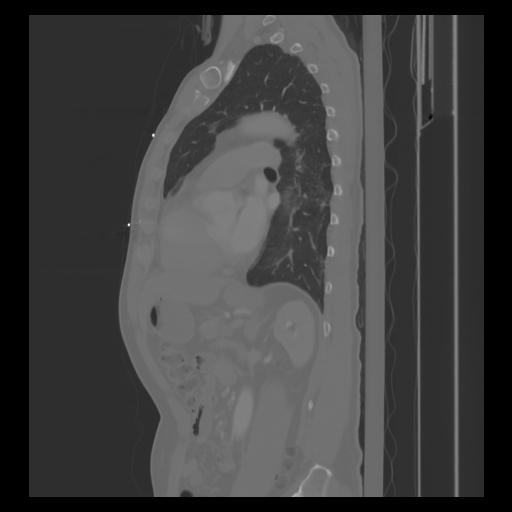

30 CUERPO,CE,Sagittal,3.000,CUERPO,Sagittal,